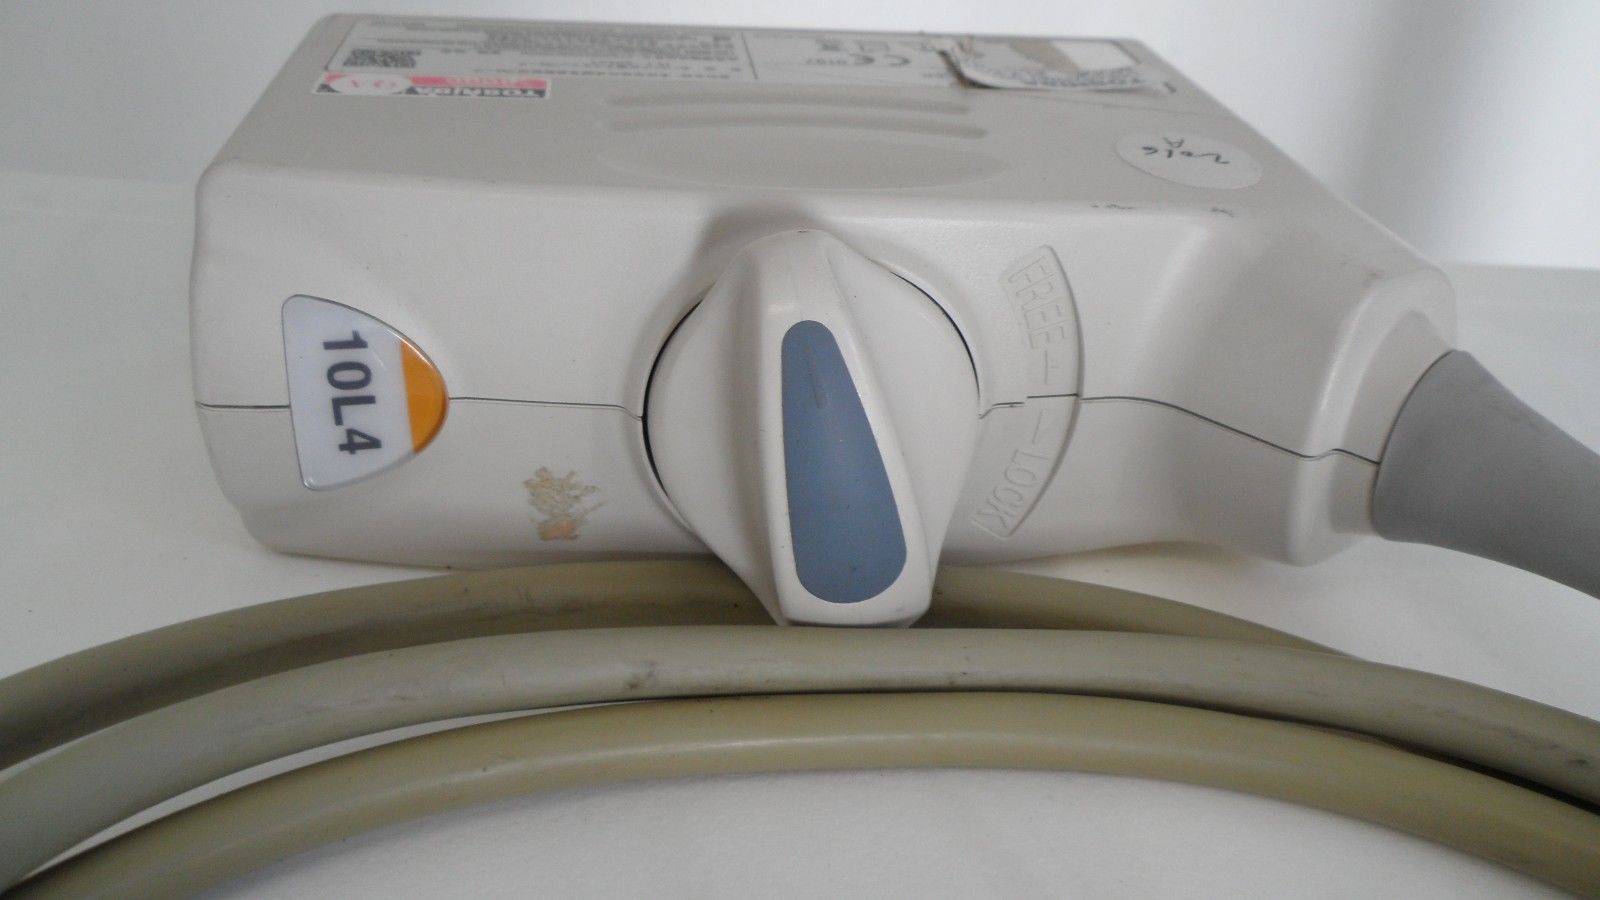

Toshiba Probes

DIAGNOSTIC ULTRASOUND MACHINES FOR SALE